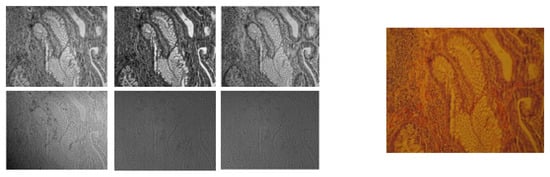

3.1. RGB vs. Multispectral Imaging